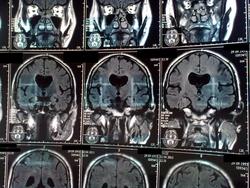

Уважаемый коллега!Большая просьба-в кадр помещать по 4 снимка максимум.

Очень мало нормальных сагиттальным снимков, хотя по СКТ видно, что ретроцеребеллярные и основная цистерны расширены-трудно оценить мозжечок.

Полость прозрачной перегородки также имеется.Гидроцефалия смешанная, преимущественно за счет внутренней.Не исключено наличие очагов глиоза субкортикально, но ( повторюсь)-по таким снимкам трудно оценить структурные изменения.

отсутствие прозрачной перегородки- гипо или агенезия, диспластические изменения каудальных отделов червя мозжечка с компенсаторным цистернальным расшиернием в ЗЧЯ. Расшиерны толко боковые желудочки, III-ий не изменен. Обезыствлены хориоидальные сплетения. Уменьшен объем мозжечка. Перивентрикулярно определяются горизонтальные и вертикальные поввышенные по Т2 ВИ -похоже на артефакты. Это все, что удалось разглядеть. Можно предположить развите спино-церебеллярной дегенерации.